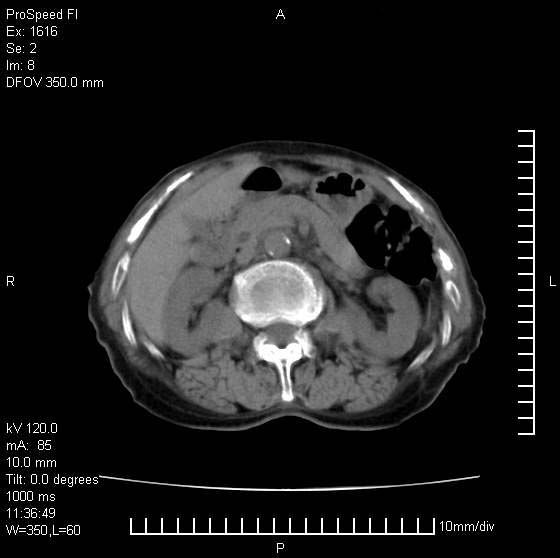

患者无明显临床症状,肝左叶发现一个圆形密度不均的低密度灶,边界较清楚,大小37x45mm,ct值35-70,患者犹豫做增强,如有增强片,我再发上,现先请各位老师会诊.

左肝外叶可见较大圆形低密度影,病灶可见较光整清晰边界,病灶内可见多量条状稍高密度影,右肝前叶亦可见圆形结节状低密度影,边界清晰,密度均匀,考虑1肝多发囊肿,左肝囊肿内出血2肝包虫病3左巨块型肝癌出血合并右肝转移或合并右肝囊肿

左肝外叶可见较大圆形低密度影,病灶可见较光整清晰边界,病灶内可见多量条状稍高密度影

考虑:肝包虫病

肝左叶类圆形低密度影,内可见略高密度影,边界清晰周边可见环形低密度带,考虑肝腺瘤可能,建议增强扫描除外肝血管瘤与肝癌

肝左叶不均匀占位,内有斑片状高密度出血灶,内侧缘似有假包膜,腹主动脉周围及肝门区结构紊乱,似有增大淋巴结,考虑:肝左叶hcc并淋巴结转移。建议增强扫描除外其他。